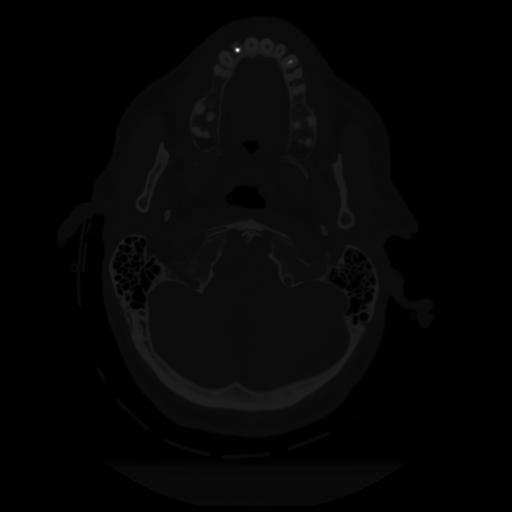

12 P.BLANDAS,,Vol,0.5,P.BLANDAS,,